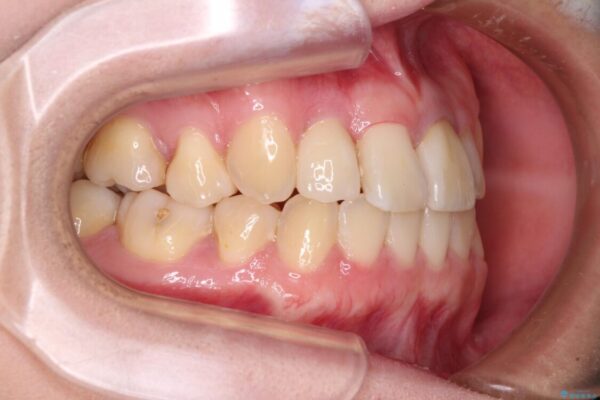

治療前

• 虫歯治療ついでに歯並びの後戻りを改善 インビザラインによる矯正治療 治療前画像